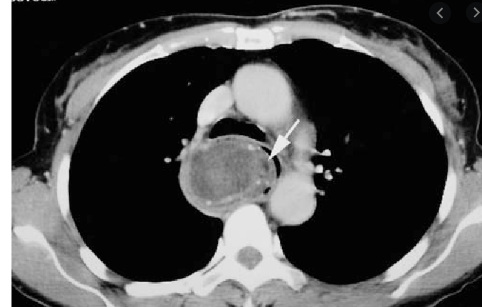

70 anos, masculino

Disfagia.

Leiomioma do esôfago

Neoplasias benignas do esôfago são raras (<1% dos tumores do esôfago)

TC: Massa intramural, bem definida, circunscrita, arredondada; densidade de partes moles; calcificação é quase patognomônico; realce difuso discreto / moderado pelo contraste.

Tumores pequenos < 5 cm geralmente são assintomáticos; tumores maiores podem causar disfagia, obstrução, tosse e sangramento.